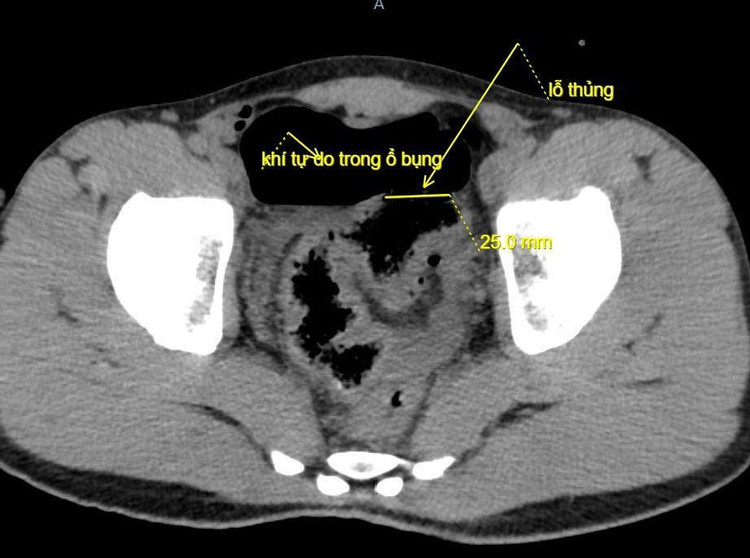

Ê-kíp phẫu thuật tiến hành mổ mở bụng thăm dò, phát hiện ổ bụng có khoảng 100ml máu và dịch bẩn. Đại tràng sigma có đoạn tổn thương dài 5cm, lỗ thủng khoảng 2cm, xung quanh dập nát. Bệnh nhân được cắt lọc lỗ thủng, khâu đoạn đại tràng tổn thương, làm sạch ổ bụng và đặt dẫn lưu. Sau phẫu thuật, bệnh nhân được điều trị tích cực bằng kháng sinh, bù dịch, giảm đau và dinh dưỡng hợp lý. Hiện tại bệnh nhân tỉnh, tiến triển tốt, hết đau bụng, bụng mềm, trung tiện được.

Ảnh chụp cắt lớp vi tính ổ bụng/ Ảnh BV